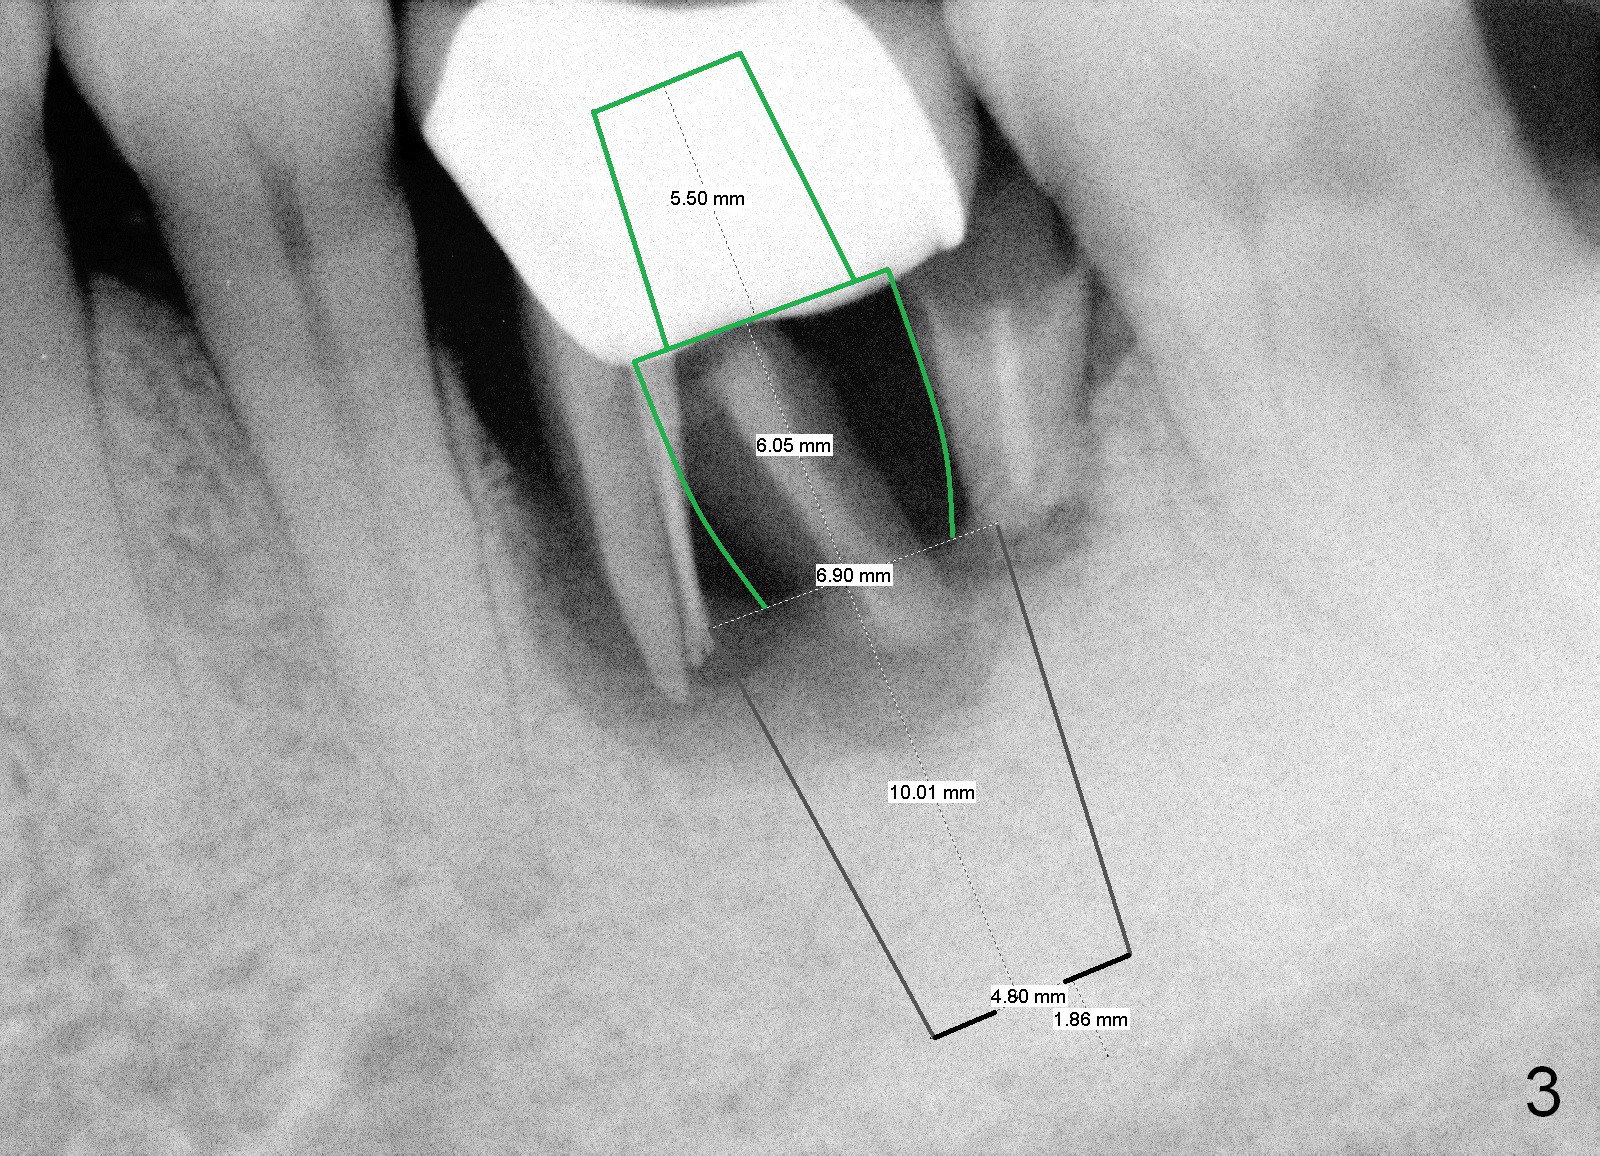

An immediate implant is to be placed deep (Fig.3 black area; 6.9x10 mm SM) because of severe bone loss. The cemented abutment (green area) should be long (length 5.5 mm, cuff 6 mm). The diameter of the abutment should be 6.8 or 7.8 mm.